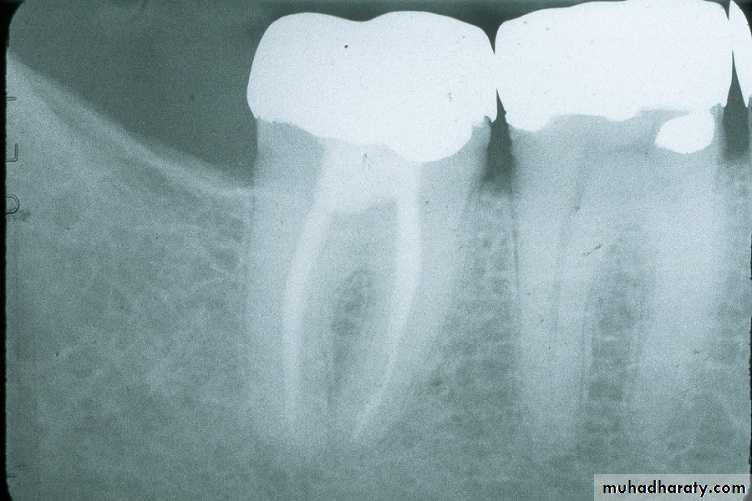

In the paralleling technique( the illustration above left), the film is positioned in the mouth so that the long axis of the film and the long axis of the tooth are parallel.

In the illustration above right, the film is placed straight up and down and is not parallel; the patient is unable to close completely on the biteblock and the apices of the teeth would not appear on the film.

The film above right shows the result of the patient not biting on the biteblock. The apices are cut off.